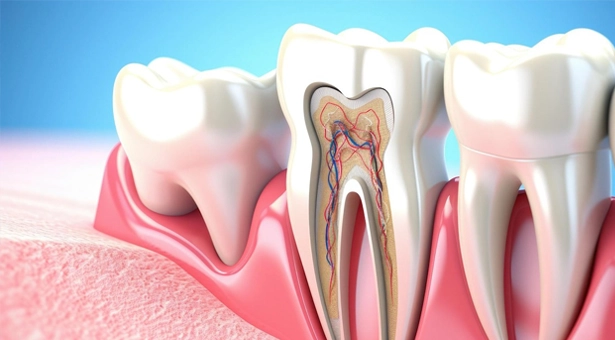

Rotary Endodontics Handpiece